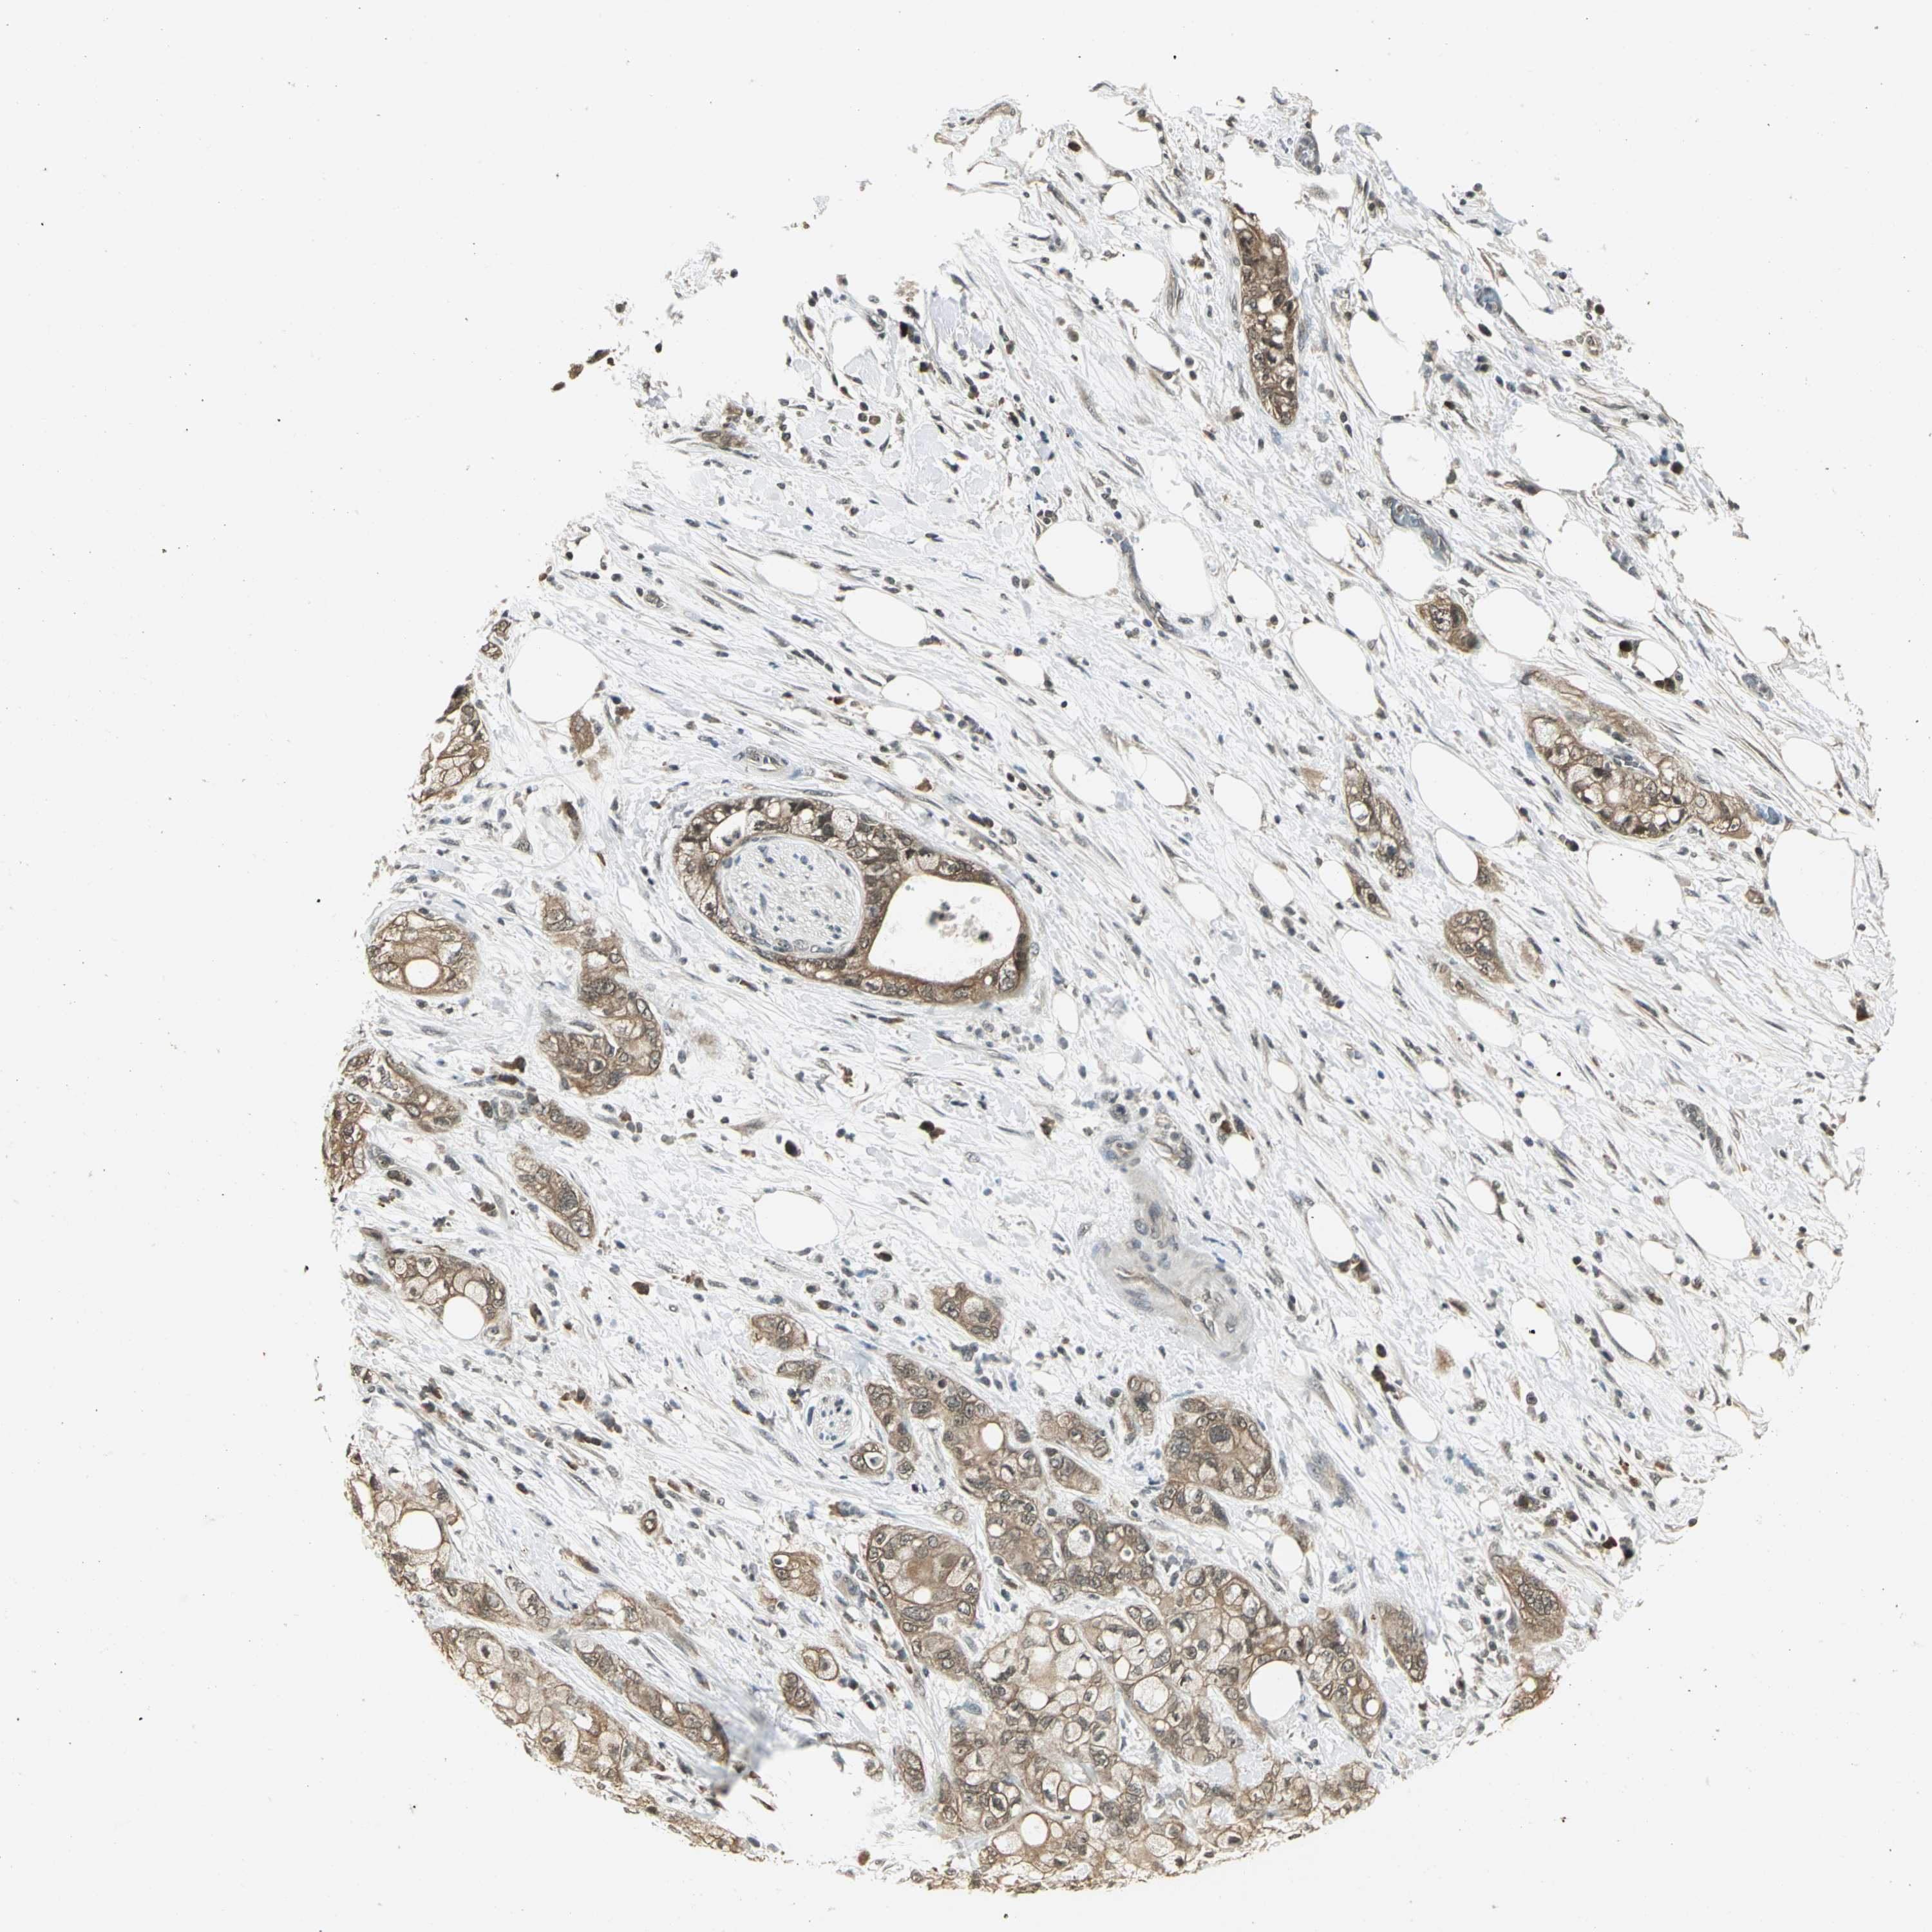

PANCREATIC CANCER - Protein expressioni

A mouse-over function shows sample information and annotation data. Click on an image to view it in a full screen mode. Samples can be filtered based on level of antibody staining by selecting one or several of the following categories: high, medium, low and not detected. The assay and annotation is described here.

Note that samples used for immunohistochemistry by the Human Protein Atlas do not correspond to samples in the TCGA dataset.

Antibody stainingi

Antibody staining in the annotated cell types in the current human tissue is reported as not detected, low, medium, or high, based on conventional immunohistochemistry profiling in selected tissues. This score is based on the combination of the staining intensity and fraction of stained cells.

Each image is clickable and will lead to virtual microscopy that enables deeper exploration of all samples and also displays staining intensity scores, fraction scores and subcellular localization as well as patient and tissue information for each sample.

Antibody HPA002382

Antibody CAB005109

Antibody CAB047311

Staining

High

Medium

Low

Not detected

Intensity

Strong

Moderate

Weak

Negative

Quantity

>75%

75%-25%

<25%

None

Location

Nuclear

Cytoplasmic/membranous

Cytoplasmic/membranous,nuclear

Adenocarcinoma, NOS

Adenocarcinoma, metastatic, NOS